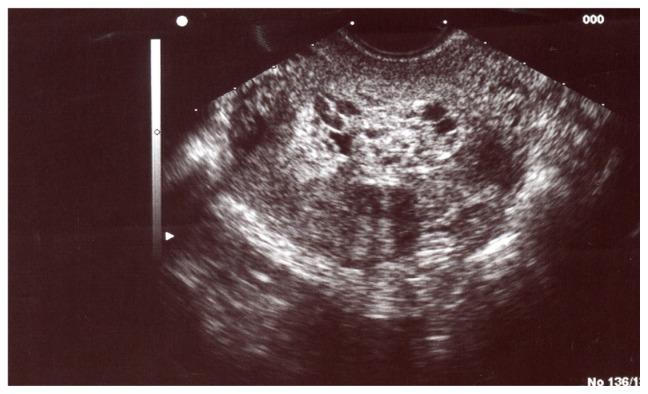

The authors report a case in which a molar pregnancy was mistaken for an ectopic pregnancy in the early first trimester. This confusion delayed diagnosis and caused distress; follow-up led to the final diagnosis of complete hydatidiform mole. Correct preoperative diagnosis of molar pregnancy by ultrasound in early pregnancy may be tricky. It is important to obtain histological evidence to make the final diagnosis of gestational trophoblastic disease. While relatively rare, consideration of molar pregnancy in the differential diagnosis of early pregnancy loss may avoid unnecessary distress.

作者报告了一例早期妊娠误诊为异位妊娠的病例。这种混淆导致了诊断的延迟,并造成了困扰;随访导致了完全性葡萄胎的最终诊断。在孕早期通过超声正确诊断葡萄胎可能具有挑战性。获得组织学证据以做出妊娠滋养细胞疾病的最终诊断非常重要。虽然葡萄胎相对少见,但在早期妊娠丢失的鉴别诊断中考虑葡萄胎可能避免不必要的困扰。